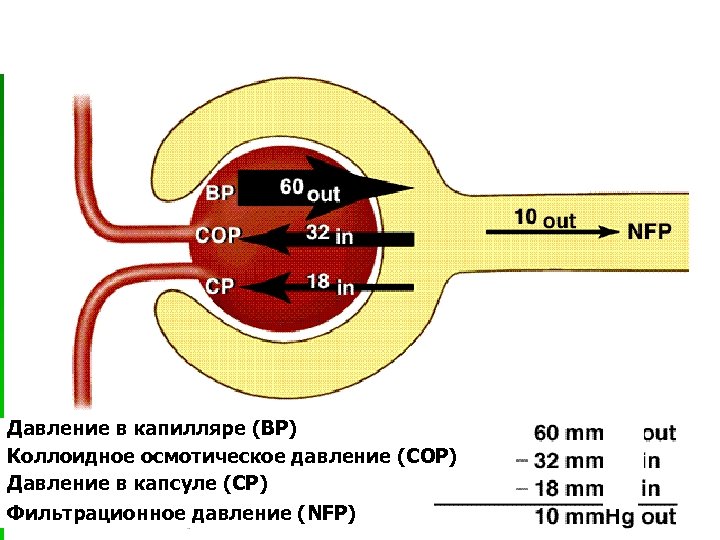

Давление в капилляре (ВР) Коллоидное осмотическое давление (СОР) Давление в капсуле (СР) Фильтрационное давление (NFP)